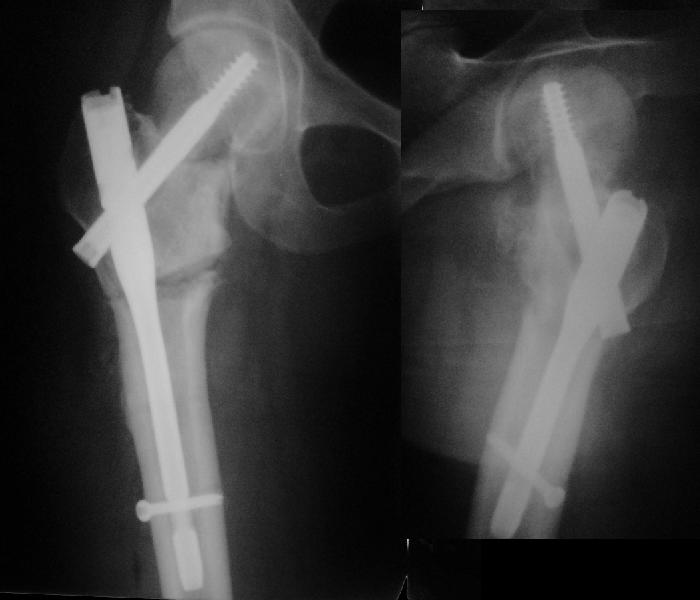

В итоге что-то такое и сделали. Убрали DHS, остеотомия, синтезировали

Affixus с небольшой вальгизацией. Снимки в приложении.